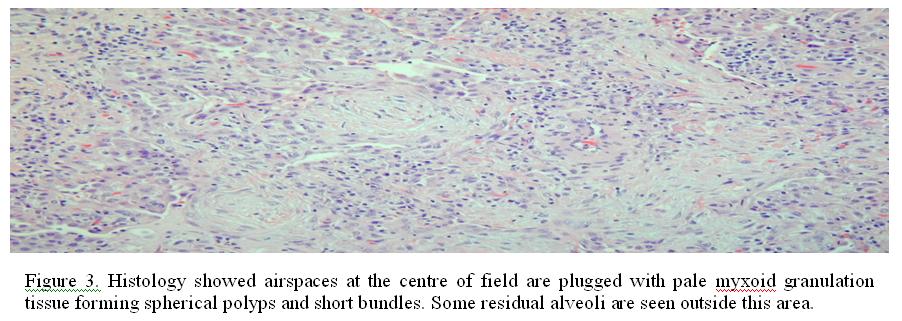

A course of intravenous timentin was started and the patient was referred for open lung biopsy as there was no improvement. Histology of the lung biopsy showed airspaces plugged with pale myxoid granulation tissue forming spherical polyps and short bundles, consistent with bronchiolitis obliterans organizing pneumonia (BOOP) (Figure 3).